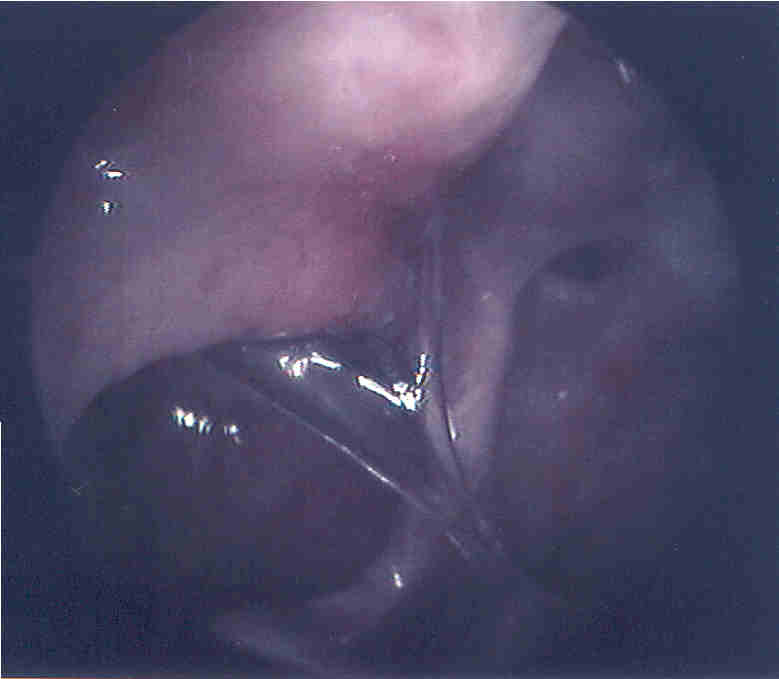

The patient in thes two pictures had recurrent sinus difficulties following sinus surgery.  He described thick mucus (behind uncinate remnant above) expelled from his nose which brought temporary relief, but the problem would recur.  At surgery he was found to have a complete ring of thickened mucus travelling between his natural and iatrogenic/accesory ostia.  Below: a suction tip is just visible inferiorly pulling on some tenacious, translucent nasal mucus.  The ostia were connected to eliminate this "recirculation ring" effect.